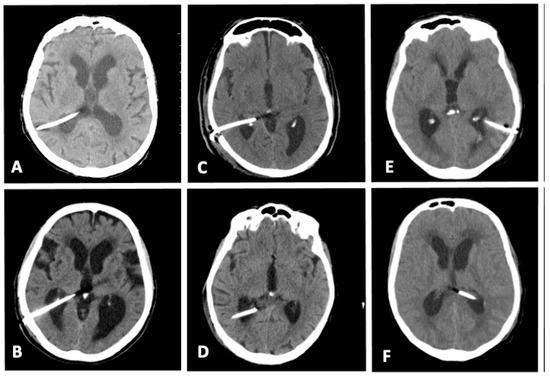

| Ventricular catheter positioning according to Hayhurst grading | Grade 1: 171 (90.1%) Grade 2: 9 (4.8%) Grade 3: 8 (4.3%) |